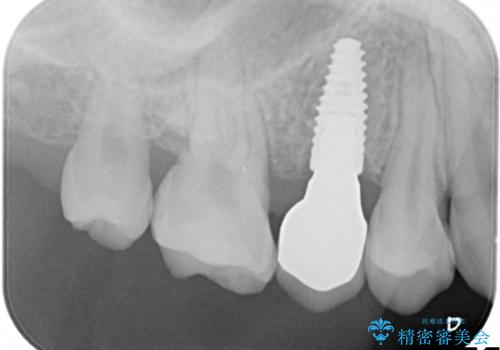

根管治療時に穿孔部位を認め、MTAにて修復し、分岐部の歯周ポケットおよび骨欠損に対しては、再生治療を行うことで、正常な歯周状態の獲得ができました。

歯冠修復はオールセラミッククラウンで行なっております。